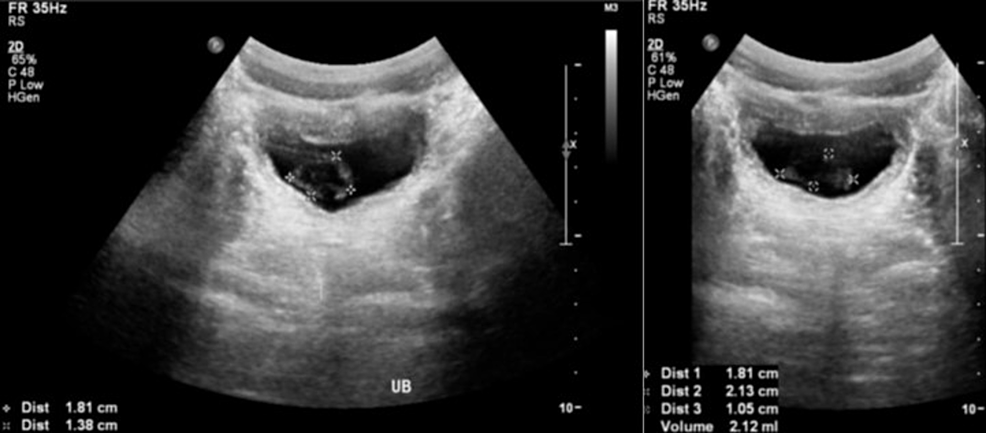

Renal ultrasound showed a urinary bladder wall thickness of 0.3 cm in a full bladder with luminal mobile echogenic foci at 2 cm x 1.3 cm. Otherwise, both kidneys were healthy in size, echogenicity, and corticomedullary differentiation with no hydronephrosis or ureteronephrosis (Figure 2).